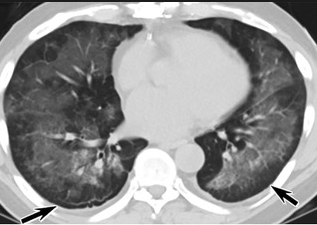

更值得注意的是,有之前应对过武汉新冠疫情的中国权威肺病专家,在查阅了60篇涉及美国“电子烟肺病”病例的研究论文,并对其中142位电子烟肺病患者的250张肺部影像图片、临床信息以及文献原文进行了仔细全面的研究后,发现这些病例中有16个更有可能是新冠肺炎的“疑诊患者”,有5个临床症状和治疗情况相对完整的患者,还被这些专家认定为了“中度可疑”。另外,这16个病例中有12个病例的发病时间,都在2020年以前。

(这4张图,是专家怀疑被误诊为电子烟肺病的其中一个病例的肺片。专家表示,他们不是仅仅通过一张影片做判断的,而是通过这4张涵盖了这名病例肺部多天变化情况的影片进行的研判,认为该病例的病程进展跟新冠更为相似)